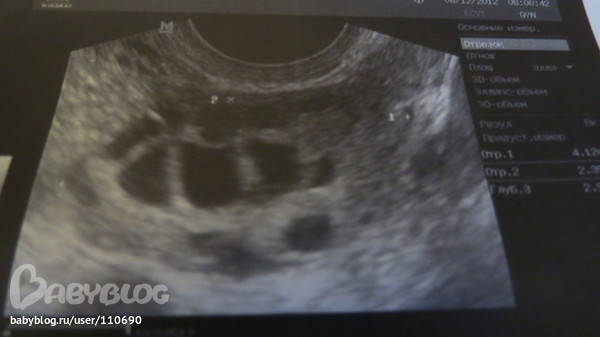

Ну вот и сходила на Фолликулометрию

Да видимо мне повезло, т.к она увидела фолликул и там жалостливо посмотрела, так сожалела,что наверно он не вылупится((( но я пойду на узи на 21 день,хочу посмотреть, что узи покажет. Теперь только узи, строго 3 раза в месяц.Тесты больше не покупаю.

У меня точно такая же ситуация! Повышенный пролактин, но я его понизила с помощью бромокриптина, до сих пор пью его каждый день по 1 таблетке. И держу на контроле. И с фолликулами та же история, сказали мультифолликулярные, их много, но доминантного нет! У меня повышен вес от нормы на 25 кг, и мне гинеколог сказала худеть обязательно. Потому что это влияет на О. Вот теперь пытаюсь сбросить вес(( и надеюсь на чудо, нельзя опускать руки. Все у нас получится!